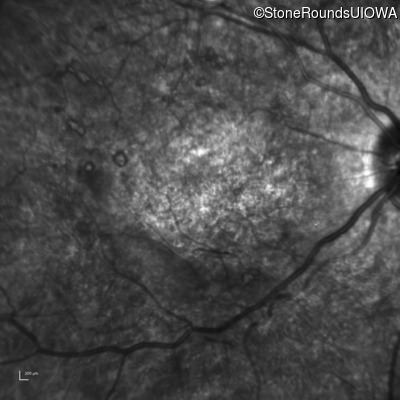

Infrared Fundus Photograph - Right - 20/400 sc

Exemplar